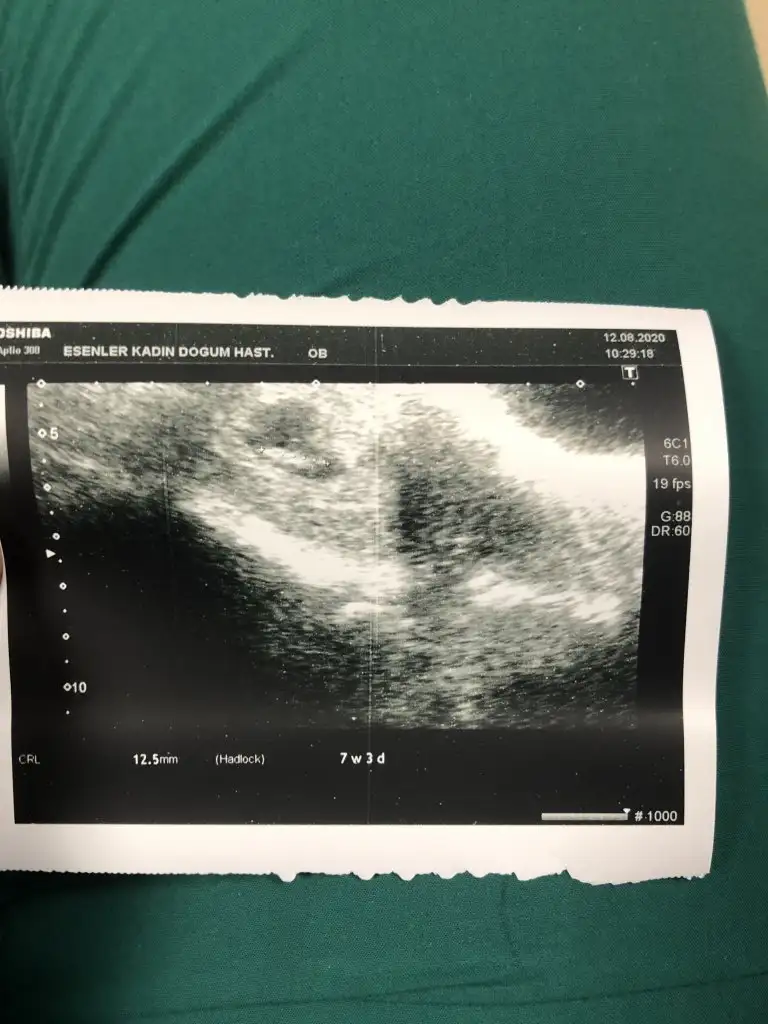

Karından bakıldı ise kız sanki 11 12 13 haftalar olmalıBenim de bugün 7+3 tahmin alabilir miyim